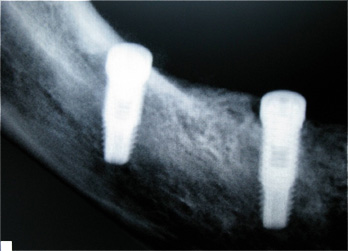

Resultado de colocação de implante dentário na Clínica São Filinto

Caso 5 - Colocação de implantes dentários e reabilitação com pontes em zircónio cerâmica para reabilitação dos dentes ausentes do 3º e 4º quadrantes.

![]() |